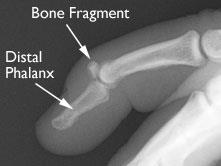

When the fracture is large and causes joint damage, the decision may be made to operate on the finger for the best results. See the best & latest mallet finger pinning cpt code on iscoupon.com. Surgery was performed by dorsal extension block pinning with percutaneous curettage at 49 weeks after the injury. Mallet finger is an injury to the tip of the finger when something hard, like a baseball, jams it. Mallet finger refers to injuries of the extensor mechanism of the finger at the level of the distal interphalangeal joint (dip). Commonly an athletic injury, mallet finger occurs when the outermost joint of the finger is injured. A mallet finger describes a condition in which the end of a finger is bent (flexed) towards the palm and cannot straighten. A mallet finger, also known as hammer finger or plf finger, is an extensor tendon injury at the farthest away finger joint. The term mallet finger has long been used to describe the deformity produced by disruption of the terminal extensor mechanism at the distal interphalangeal (dip) joint. This joint is often injured during activities such as baseball. (surgery may be advised straightaway if there is a cut to your finger; This results in the inability to extend the finger tip without pushing it. In these cases, pins, wires or even small screws are used to secure the bone fragment and realign the joint (see figure 4).

In these cases, pins, wires or even small screws are used to secure the bone fragment and realign the joint (see figure 4). Approximately ten days after surgery you will meet back up with your doctor to remove the sutures and monitor the progress of the healing. Mallet joint is an injury to the distal interphalangeal, or dip, joint of the finger. See the best & latest mallet finger pinning cpt code on iscoupon.com. Below are 45 working coupons for mallet finger pinning cpt code from reliable websites that we have updated for users to get maximum savings.

Doyle's classification of mallet finger injuries. In these cases, pins, wires or even small screws are used to secure the bone fragment and realign the joint (see figure 4). Treatment options include splinting and surgery, in some cases. Surgery is needed to repair the torn tendon if the above fails. However, most injuries that cause mallet finger. If your injury is more severe (for example, if a bone is broken or a joint is out of place), you may need surgery. Surgery is only needed if you also. They are the most prevalent finger tendon injury in sport. Stax finger splint stax finger splints help protect fingertips and nail beds during injuries. The imbalance between flexors and extensors leads to the last joint (dip joint) appearing flexed. Mallet finger surgery involves using pins, screws or wires to realign the. These pins can be removed after two and then four weeks, after which physiotherapy treatment can resume. When you think about how much we use our hands, it's not hard to understand why injuries to the fingers are.